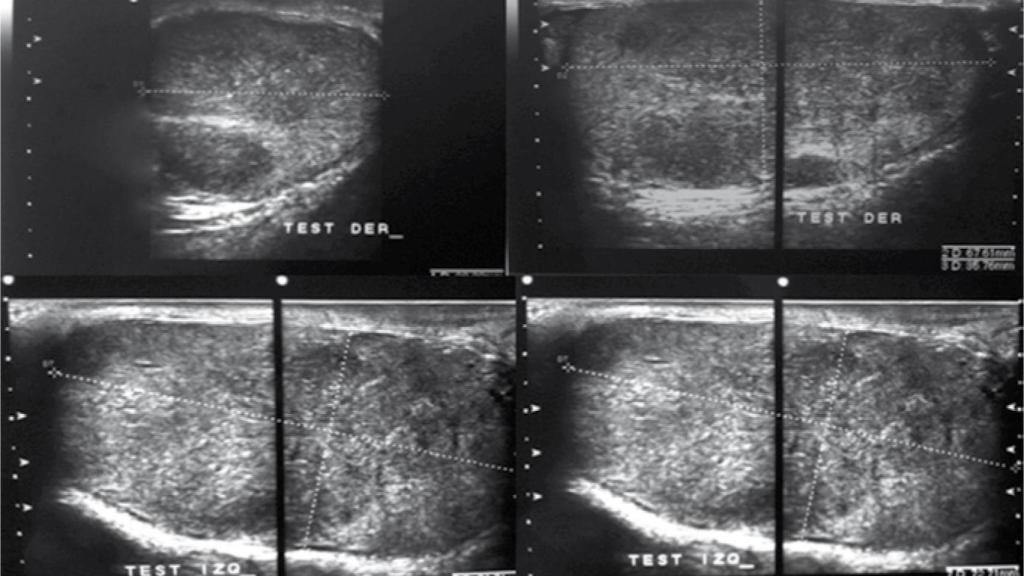

Ecografía de un tumor testicular bilateral.